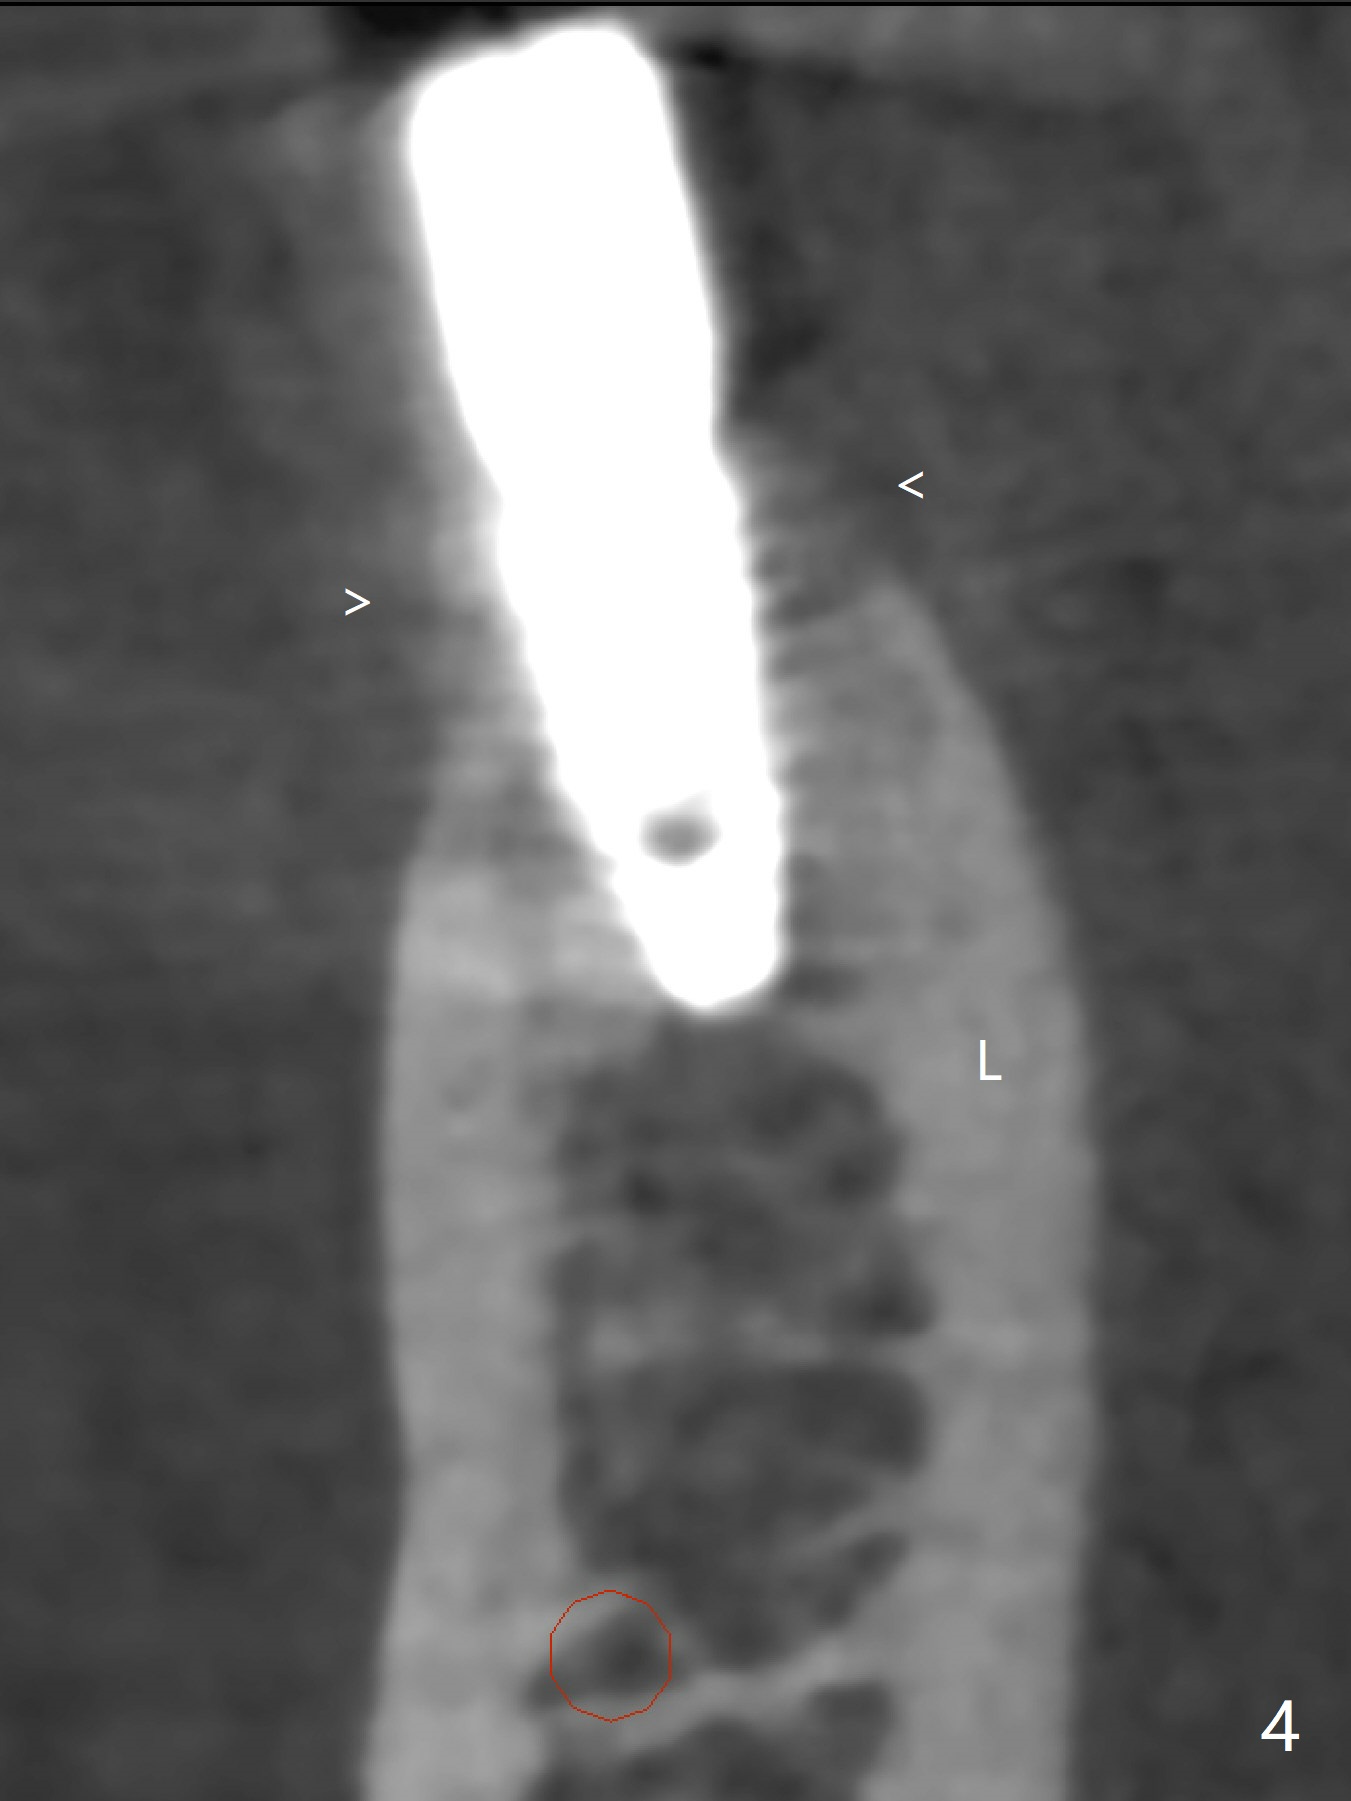

Six months post implant removal and bone graft, the patient returns for #29 implant placement with guide. With Lidocaine and Septocaine each carpule (infiltration), the patient experiences pain when the last drill used is ~ 2 mm short of designed depth. To make sure to have lingual subcrestal placement and avoid the Mental Loop, a 3.5x8.5 mm implant is placed (Fig.1,2 (3 mm shorter than the design)). Immediately postop CBCT (sagittal section) shows that the osteotomy probably hits the branch from the Mental Nerve (Fig.3 <). The coronal portion of the implant is covered with apparently grafted bone (Fig.4 <; bone density ~ 1,000 Hounsfield units; L: lingual). The implant will be loaded longer than 4 months due to unfavorable crown/implant ratio.